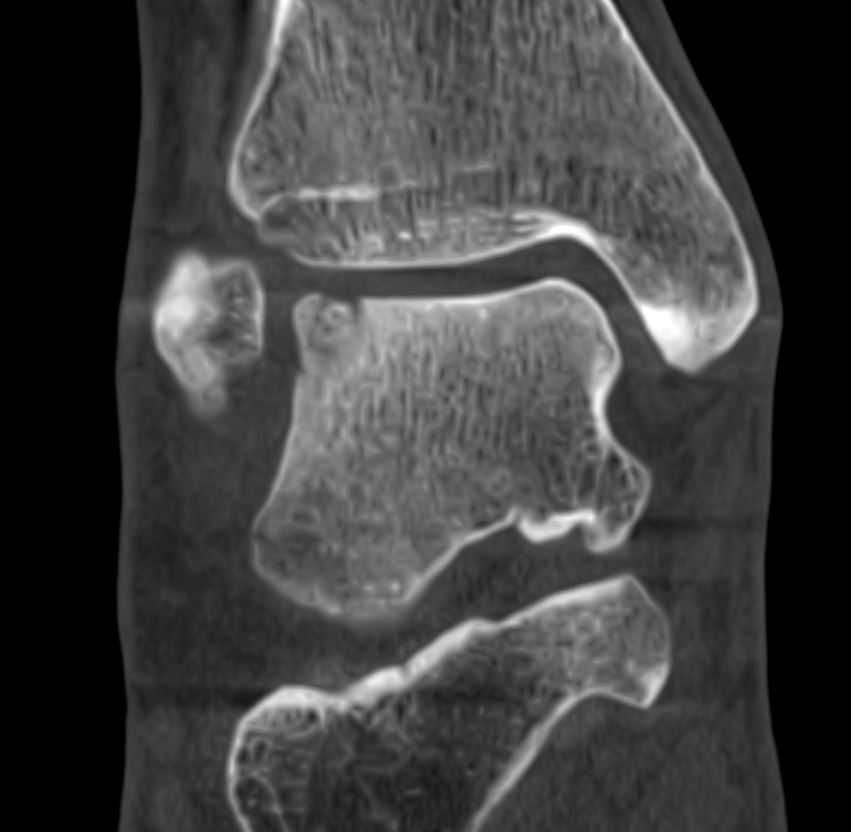

Home Schwerpunkte Krankheitsbilder Bänderriss am Sprunggelenk – exzellente Ergebnisse mit der richtigen Behandlung posttraumatische OCL lateral

posttraumatische OCL lateral